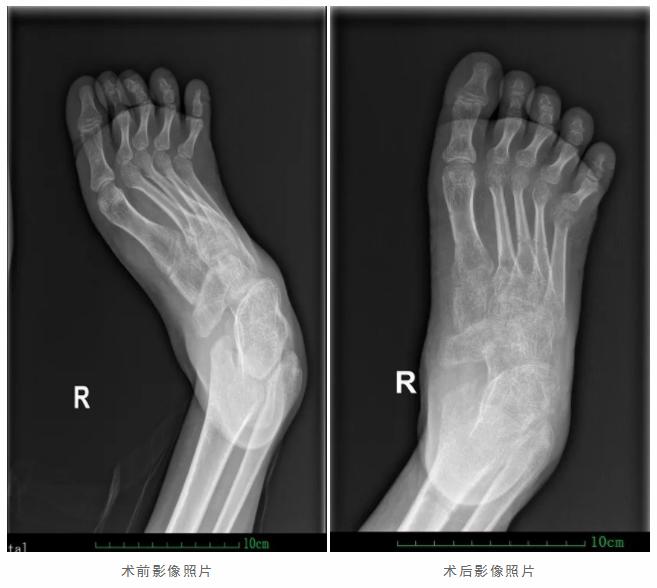

为进一步解决患者下肢足部畸形的问题,2019年10月,郑炳铃团队为其实施“右侧下肢Ilizarov环形外固定架矫形术+右侧足三关节融合术”。术后,大龙畸形的“马蹄足”得到矫正,逐渐趋向正常,目前他的整个右脚脚掌能够完全着地。